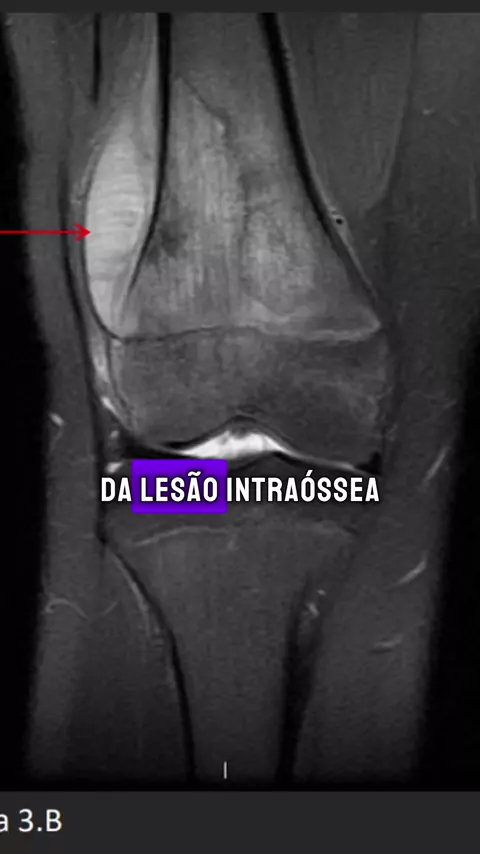

Caso clínico: dor progressiva no joelho esquerdo. #medicina #semiologia #osteossarcoma #ortopedia